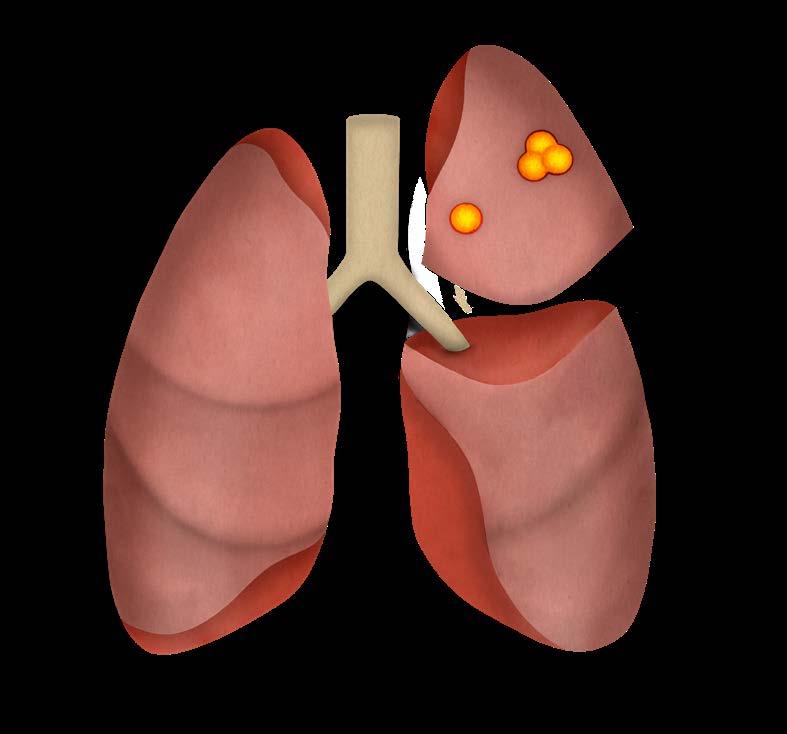

Mynd 6-1 Lítið lungnakrabbamein í hægra lunga (ör) sem fannst við skimun með tölvusneiðmyndum.

Með tilkomu tölvusneiðmyndatækni (TS) varð unnt að finna mun smærri hnúta í lungum en áður var mögulegt með hefðbundnum röntgenmyndum (mynd 6-1). Á síðustu áratugum hefur verið efnt til stórra framvirkra samstarfsverkefna, bæði í Bandaríkjunum og Evrópu. Fyrstu rannsóknir á skimun með TS voru gerðar í Japan og fyrsta alþjóðlega rannsóknin benti til þess að unnt væri að finna um